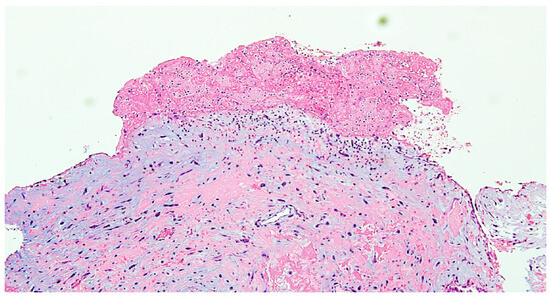

Given the critical obstructive physiology and life-threatening presentation, the patient underwent urgent surgical excision of the mass via median sternotomy under cardiopulmonary bypass (Figure 2). Upon opening the left atrium, a gelatinous mass was identified, attached to the interatrial septum via a narrow pedicle. The tumor measured approximately 3.7 × 4.5 cm and exhibited a lobulated, irregular surface (Figure 3). These findings accounted for the severe dynamic obstruction of the mitral orifice observed preoperatively and underscore the capacity of left atrial myxomas to precipitate acute, life-threatening obstructive disease. Intraoperatively, the mass was friable and gelatinous, with focal areas of increased density suggestive of fibrous components, consistent with a mixed morphological pattern. Its marked mobility and fragile texture raised concern for embolic potential, characteristic of the macroscopic features of cardiac myxomas. The tumor was completely excised at its point of attachment, without requiring interatrial septal resection or reconstruction.

Figure 2. Intraoperative view of the left atrial myxoma during surgical excision.